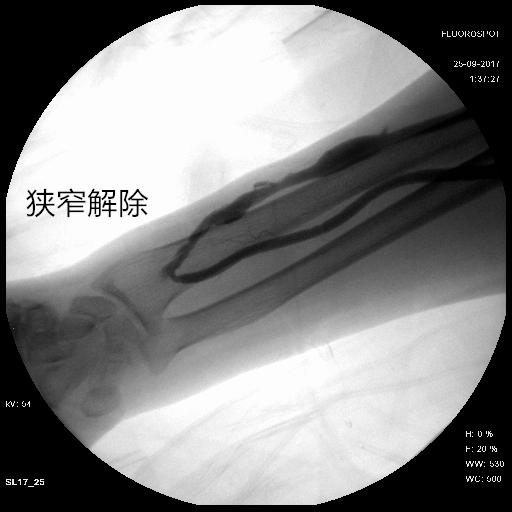

1、 经皮穿刺腔内血管成形术

简单来说就是将一个可以充气扩张的球囊进入血管腔内,然后精确输送到血管狭窄的部位,球囊充气,如气球一般膨胀,靠膨胀的力量,生生将增生的血管内膜撕开,从而将狭窄的血管扩开,这是目前内瘘狭窄应用最为广泛的治疗方法,通常在血管造影机或超声引导下进行,最大的好处就是通过像透析穿刺眼一样的创口就可以进行以上治疗,而且可以反复操作。